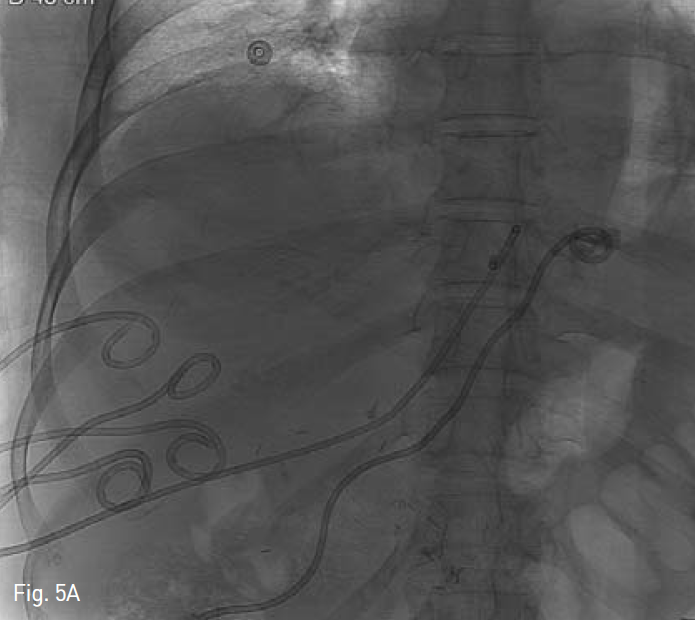

응급실 재방문 후 시행한 복부 전산화 단층촬영상 양측 간엽에 1~3cm크기의 다발성 간농양이 15일 전 퇴원 시 보다 다소 크기의 증가가 보이고, 농양 배액을 위해 다수의 농양 배액술(Fig. 5A) 및 담즙 우회를 위해 좌측 경피경간 담도 배액술(Fig. 5B)이 시행되었다. 이후 내과 및 외과 의료진과 상의 후 역행성 간농양에 대한 Anti-reflux designed, GD type stenl(Fig. 6A)를 계획하였다.

Fig. 5

After 20 days, the patient revisited our hospital with abdominal pain. We performed multiple percutaneous abscess drainage to both hepatic lobes A and left percutaneous biliary drainage B.